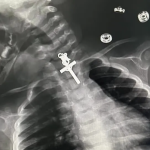

Crucifixo é detectado por meio de Raio-X na garganta de bebê de 10 meses

Criança foi levada ao hospital após a mãe perceber desconforto do bebê ao tentar engolir alimentos